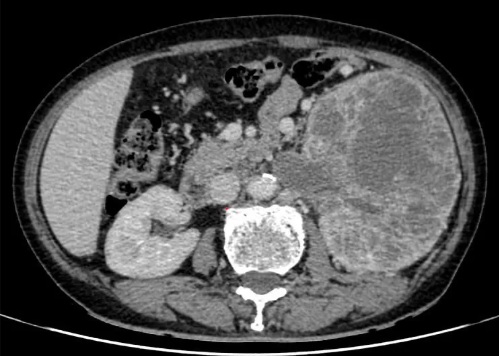

Hình ảnh chụp CT khối u ở thận xâm lấn tĩnh mạch chủ dưới. Ảnh:BVCC

Kết quả thăm khám và chẩn đoán hình ảnh cho thấy khối u ở thận trái kích thước khoảng 15 x 20 cm, phá hủy hoàn toàn cấu trúc nhu mô thận, xâm lấn đài – bể thận. Đáng chú ý, khối u đã gây huyết khối trong tĩnh mạch thận, lan tới tĩnh mạch chủ dưới, làm tăng nguy cơ tắc mạch hoặc thuyên tắc mạch phổi đe dọa tính mạng.